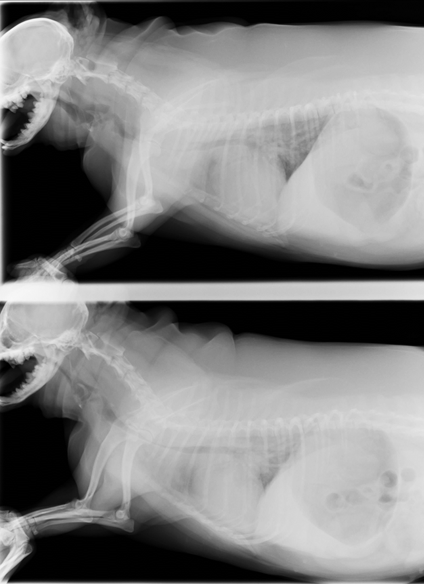

すぐに酸素吸入処置を行い、その後レントゲン検査にて頸部気管が潰れている気管虚脱を起こしていることが分かりました。

吸気、呼気状態の両方とも頸部の気管が潰れています。これでは呼吸もうまくできません。

術後のレントゲンです。気管の拡張が確認できました。呼吸状態も安定し、術後3日で退院することができました。今では元気一杯です!